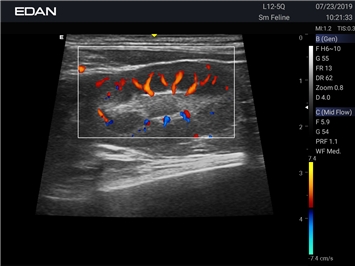

Ветеринарный ультразвук одним нажатием. Система Acclarix AX3 VET разработана с целью обеспечить бескомпромиссную производительность по доступной цене. Наличие уникальных двойных разъемов и двойных аккумуляторов в легком корпусе массой 4,5 кг из магниевого сплава позволяет системе Acclarix AX3 VET удовлетворять все потребности ветеринарных исследований, сохранив низкую стоимость.

EDAN Acclarix AX3 VET - это компактная ультразвуковая система, специально разработанная для ветеринарной практики, сочетающая высокую производительность с доступной ценой.

Передовые технологии визуализации

Качество диагностики:

• Революционная платформа с превосходным разрешением для глубоких структур

• Технология адаптивной визуализации тканей с автоматической оптимизацией

• Специальные настройки для исследования животных разных видов

• Двойные разъемы для быстрой смены датчиков